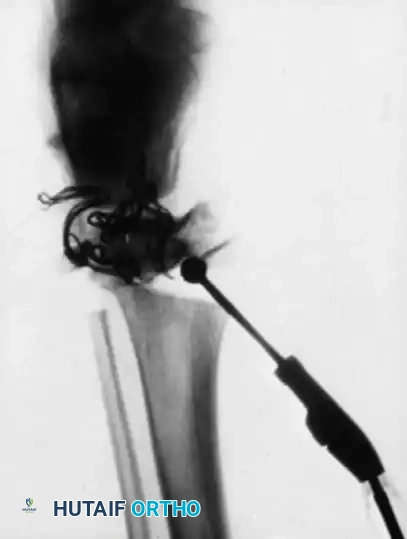

Image

Intraoperative fluoroscopy is mandatory to assess the medullary canal, which is often distorted and narrower than anticipated based on plain radiographs.

Preoperative Planning

Chotigavanichaya et al. emphasized the critical importance of determining the correct rod diameter intraoperatively. Preoperative radiographs are notoriously ineffective at predicting rod diameter due to severe bony distortion, often overestimating the medullary canal size. Repeat fluoroscopic examinations in multiple planes during surgery are mandatory.